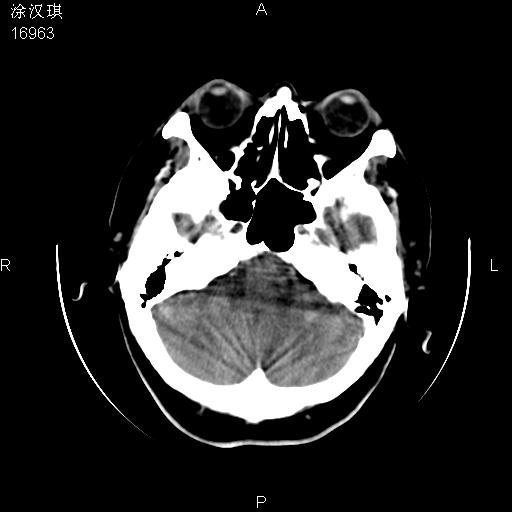

以下是引用chinazhouhua在2008-5-1 12:06:00的发言:[br]影像上来看,这是个典型的硬膜下血肿,包括右侧额颞部、大脑镰下、小脑幕下,而且在右侧额颞顶枕部、大脑镰下没看到高密度出血向脑沟内延伸,但是小脑幕下硬膜下有时候和蛛血不是很好鉴别,而且硬膜下很多时候伴有蛛血,往往在复查的时候出来,所以这种病人还是应该考虑硬膜下血肿伴有蛛血。

以下是引用zsl6918在2008-5-1 15:34:00的发言:[br]本病例主要表现为急性硬膜下血肿。